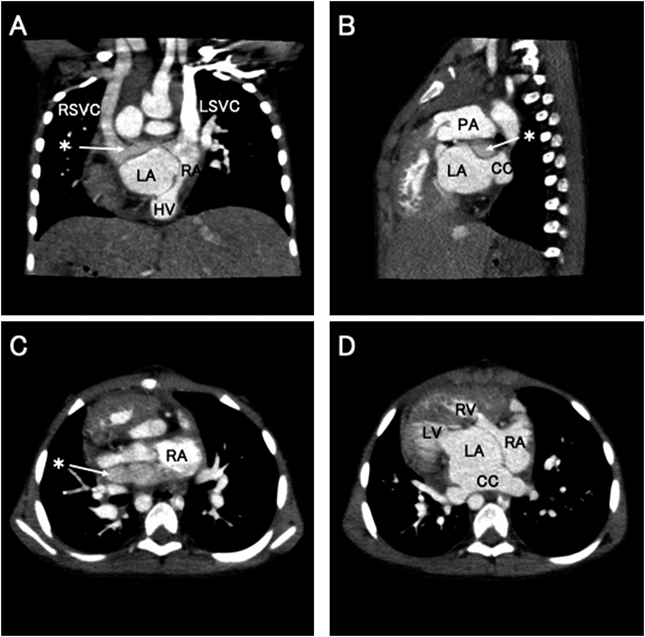

術後出血もなく初日は心房ペーシング補助で血行動態安定し,同日夜間に人工呼吸器離脱可能であった.中心静脈圧8~9 mmHgで安定していたため翌日には心房ペーシングやカテコラミンを中止した.自己脈は心拍数80~100回/分程度の接合部調律で経過し,以後も高度の徐脈は認めなかった.術後第2病日に一般病棟へ転棟し,その後も順調に経過した.術後心エコーでは両側房室弁逆流はいずれも軽度,血流転換した右上大静脈や肝静脈の血流は加速なくスムーズに左側心房である右房に還流しており,右房から右室または肺静脈から左室への流入血流障害も認めなかった.CT所見上も心房内血流転換や心房中隔形成に用いた心膜パッチの形態は問題なく(Fig. 3),体静脈還流路や肺静脈還流路に狭窄を認めず,術後第11病日に退院となった.現在,術後1年4か月経過しているが,房室弁逆流増悪や静脈還流障害など認めず,経過良好である.

Pediatric Cardiology and Cardiac Surgery 37(2): 126-132 (2021)

Fig. 3 Postoperative CT images

Postoperative cardiac morphology in the coronal view (A), sagittal view (B), and axial view (C, D). Asterisk shows intraatrial rerouting of RSVC. The CA is separated by pericardial patch without obstruction of pulmonary and systemic venous return (D). CC, common chamber; CT, computed tomography; HV, hepatic vein; LA, left atrium; LSVC, left superior vena cava; LV, left ventricle; PA, pulmonary artery; RA, right atrium; RSVC, right superior vena cava; RV, right ventricle.